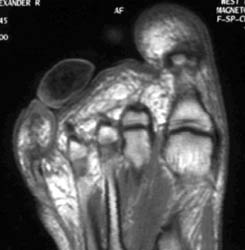

55 years old male with slowly growing mass at the tip of the plantar aspect of 4th toe. Plain films demonstrate well defined non-calcified mass at the tip of plantar aspect of 4th toe. MR imaging demonstrates this mass has low to intermediate signal intensity on all the sequences.